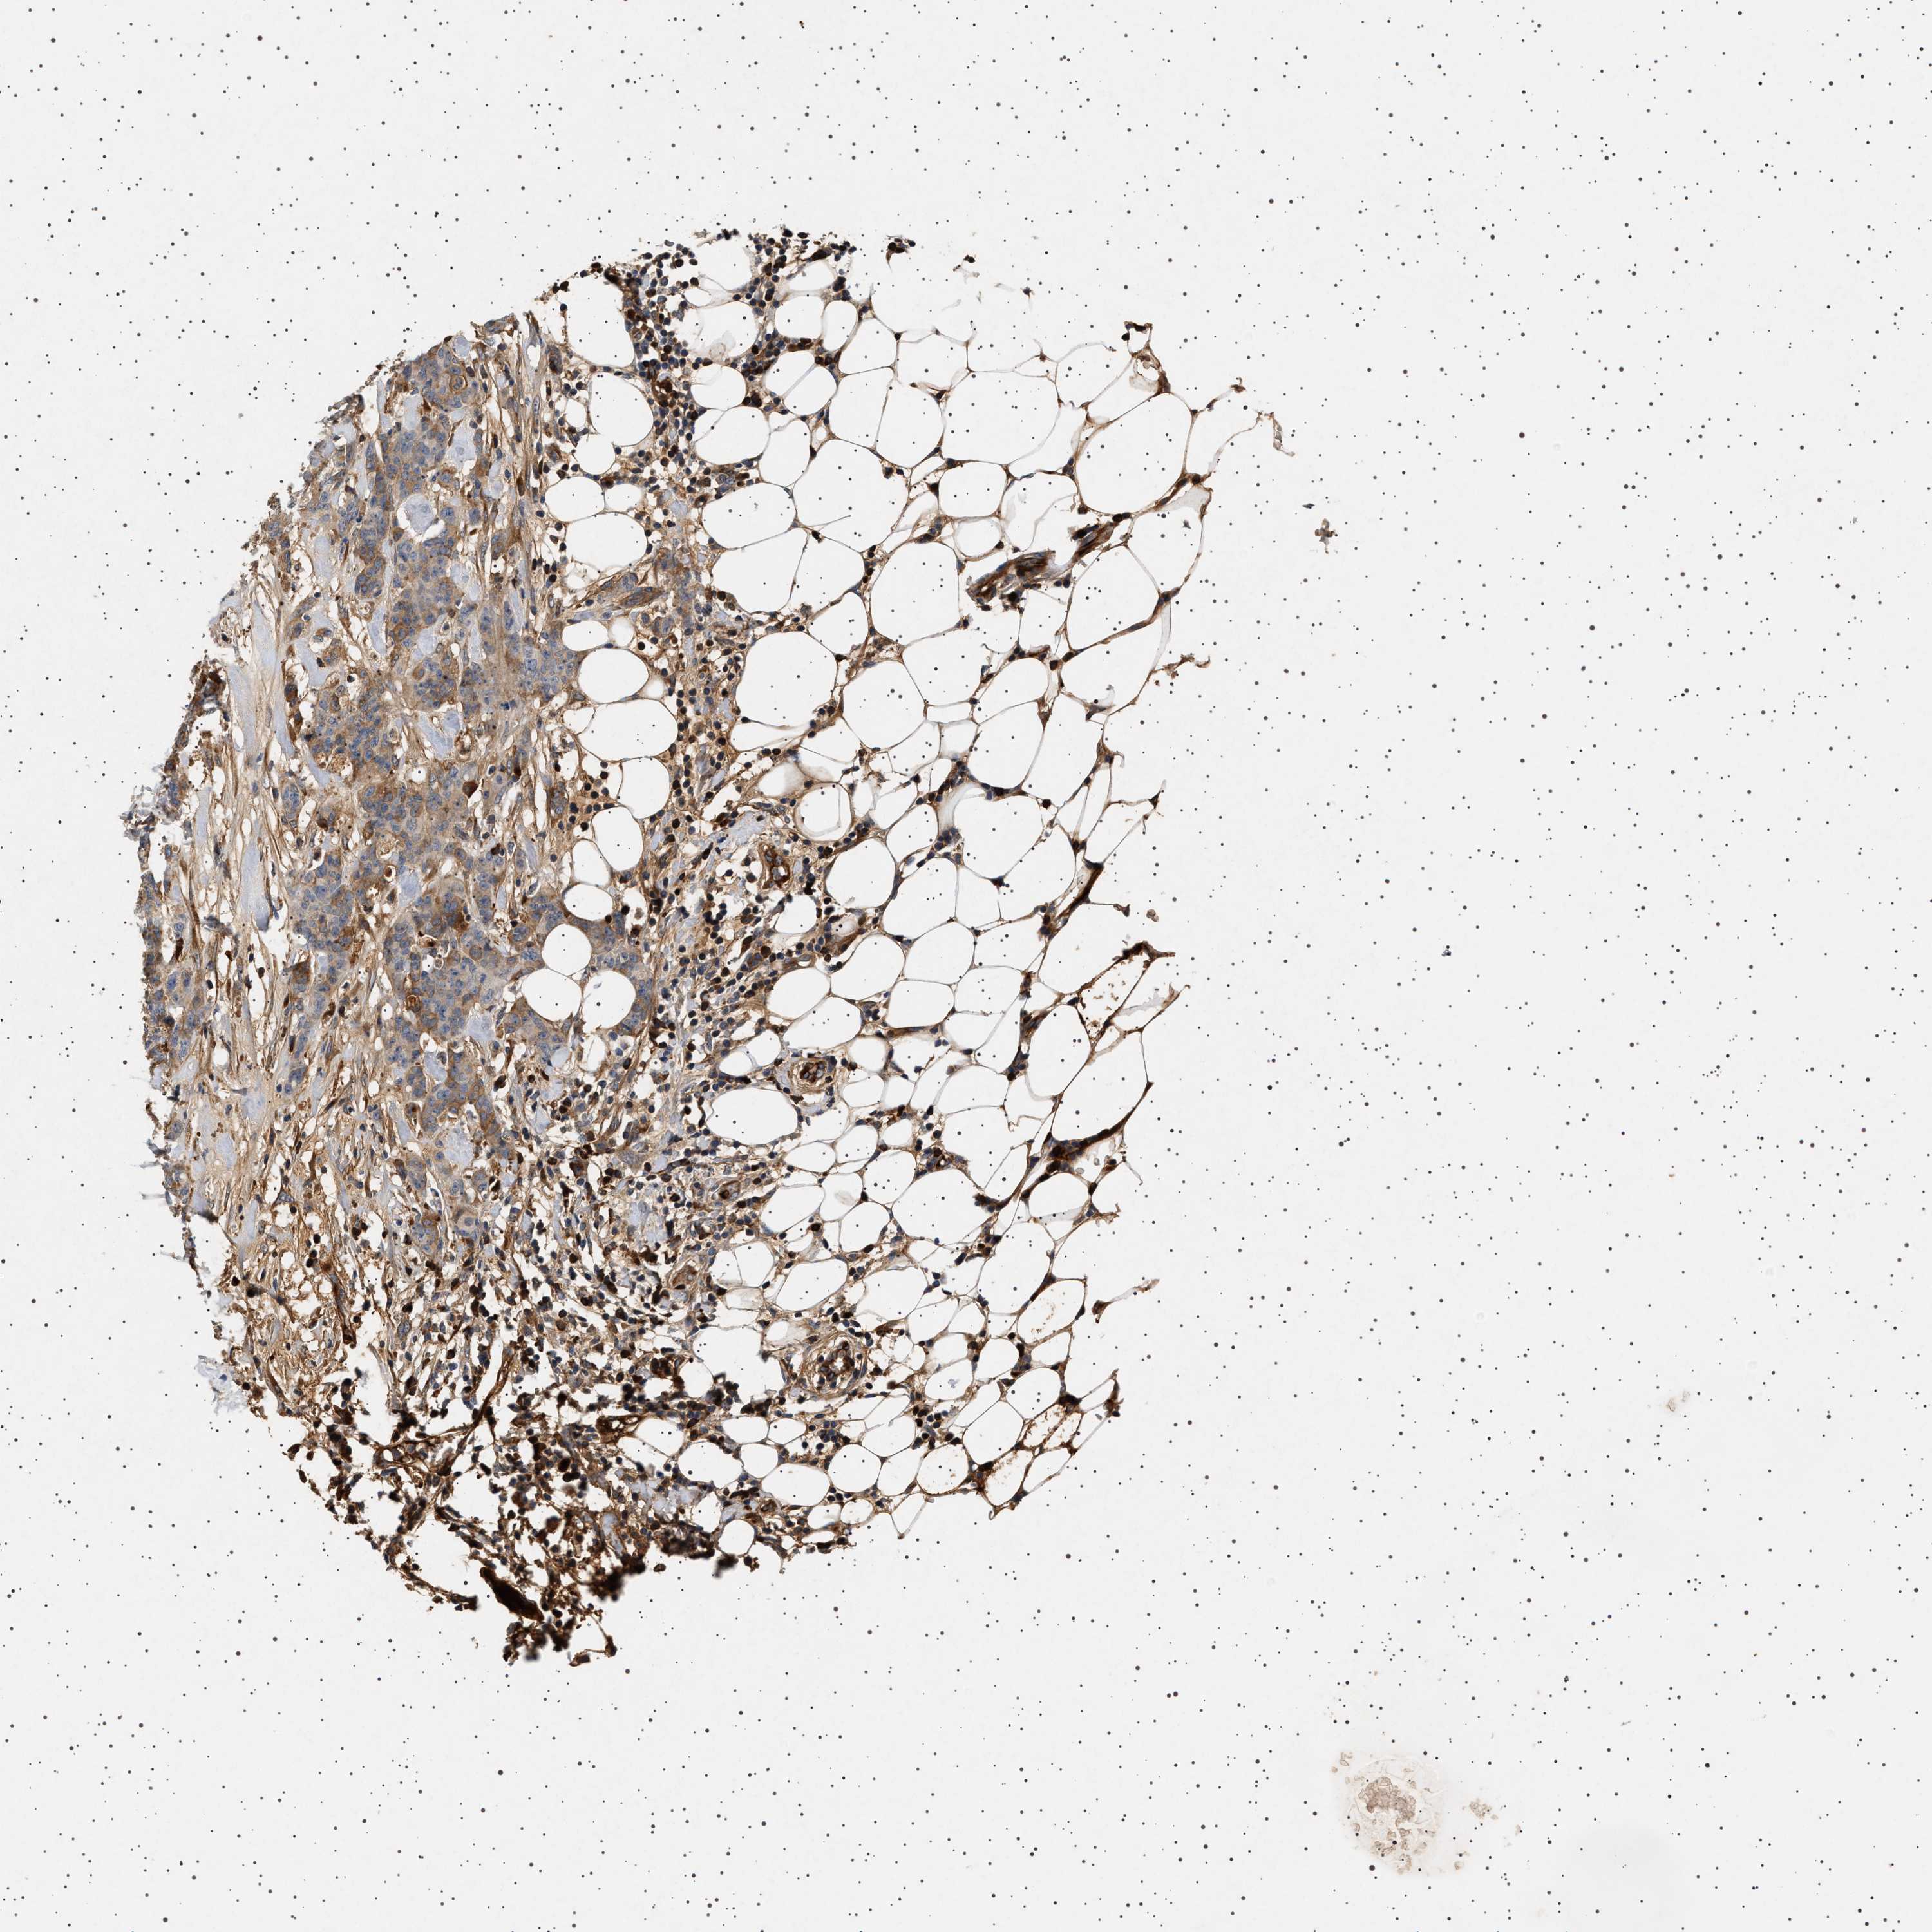

CANCER BREAST CANCER Show tissue menu

BRCA TCGA BRCA VALIDATION PROTEIN EXPRESSION

ANTIBODIES

AND

VALIDATION